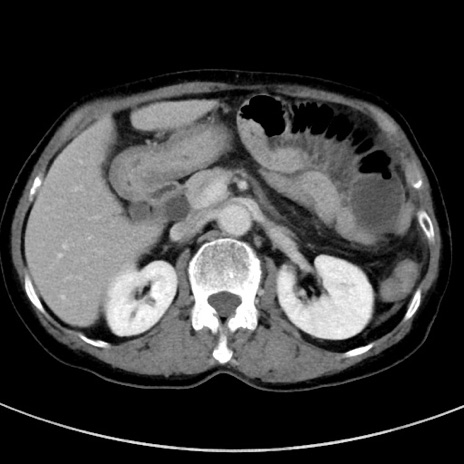

症例23(横断像)

【症例】70歳代女性

【主訴】下腹部痛・嘔吐

【現病歴】2日前より腹痛あり。昨日嘔吐あり。症状改善しないため来院。

【既往歴】胃GISTに対して胃部分切除後。

【身体所見】BT 37.1℃、BP 128/77mmHg、腹部:平坦・軟、下腹部に圧痛あり。

【データ】WBC 10200、CRP 0.31